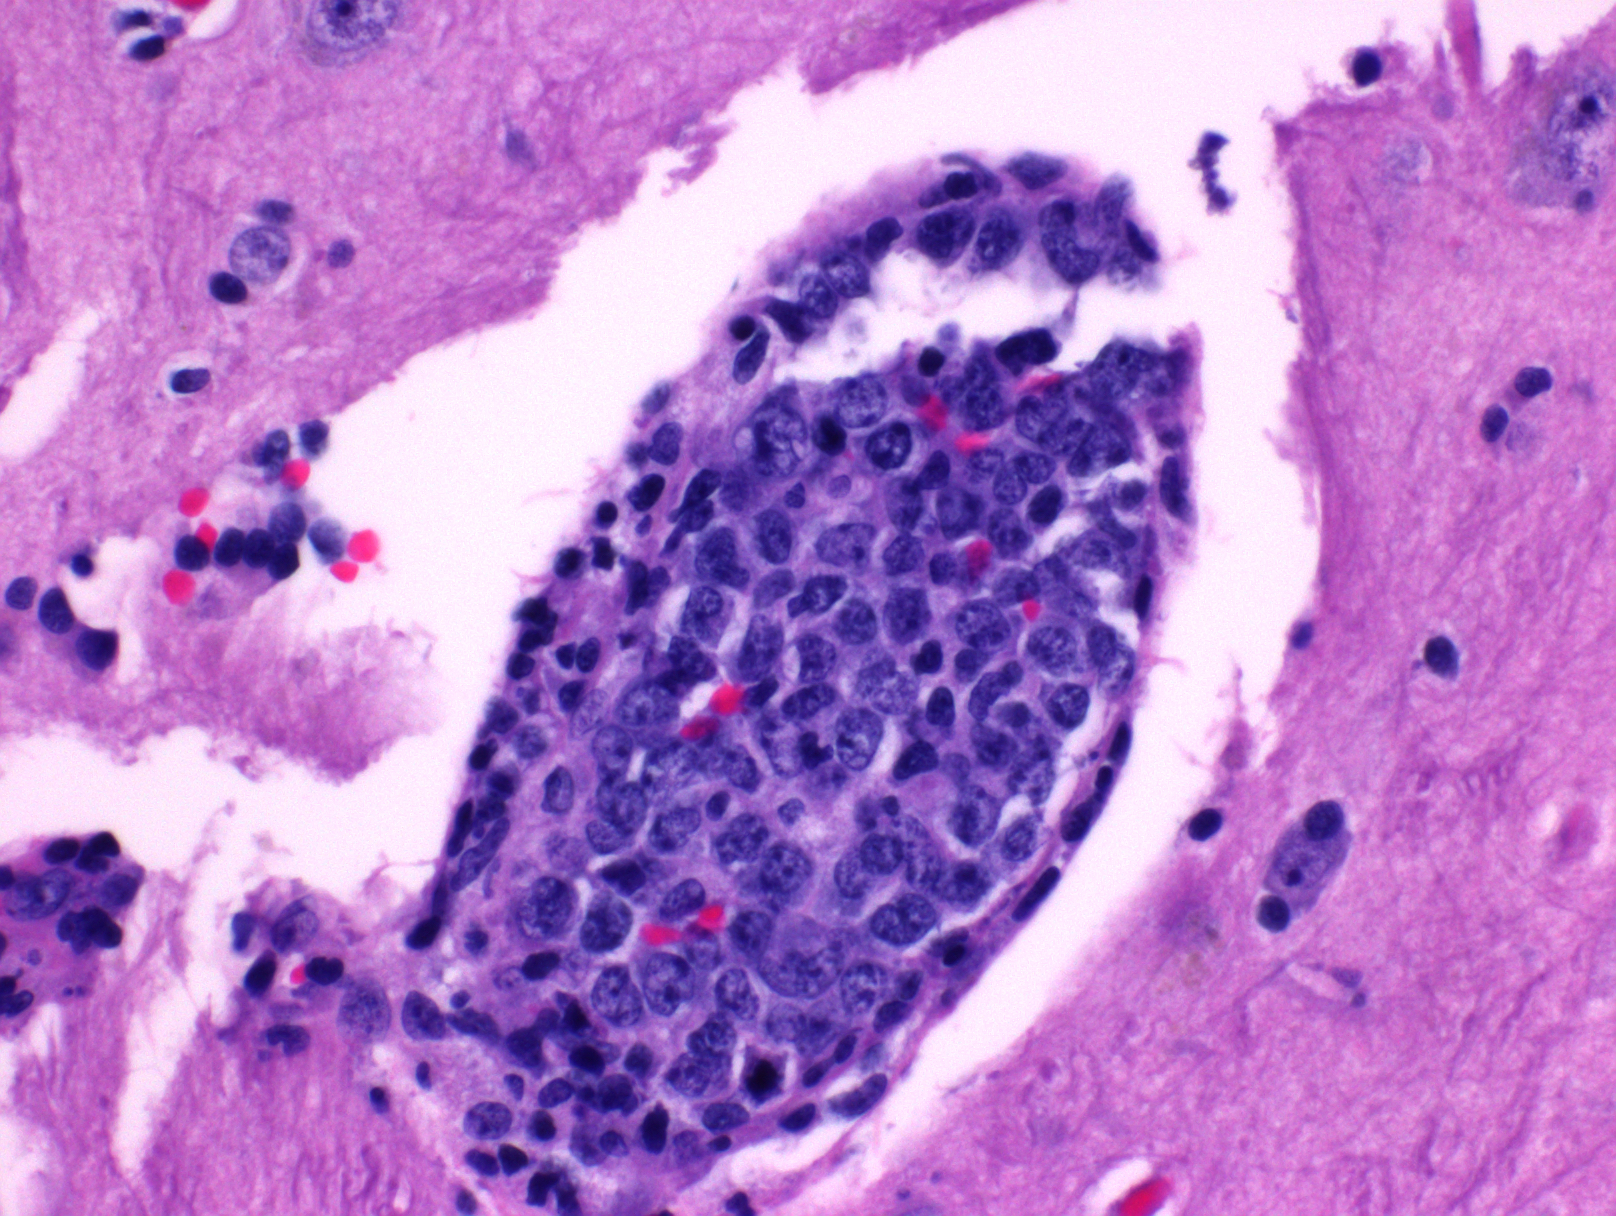

- 肿瘤淋巴细胞主要分布于小到中等血管腔内,或位于肝、脾(红髓)、骨髓的血窦内,可伴纤维蛋白血栓、出血、坏死。有时可见少量血管外瘤细胞。

- 肿瘤细胞大到中等,泡状染色质,核仁明显;有时可见粗大核染色质和不规则或锯齿状细胞核;有丝分裂像多见。